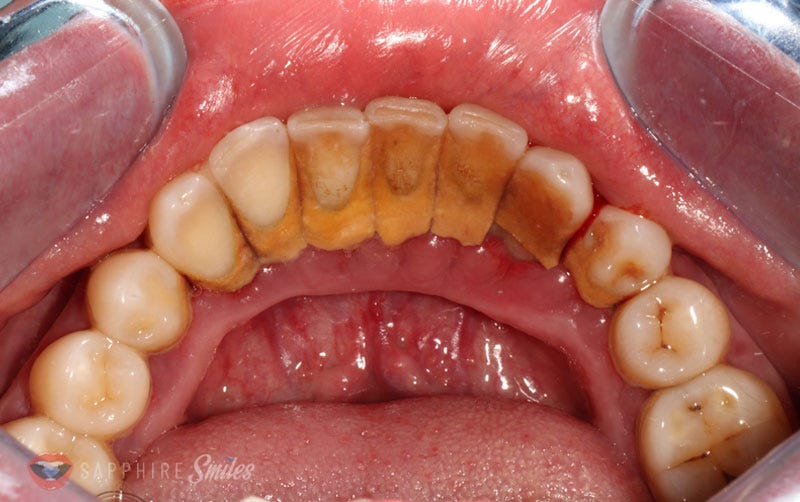

Deep Teeth Cleaning Before and After Dental Health Society What Is A Deep Cleaning For Teeth Called Deep cleaning is the term used for a periodontal treatment called scaling and root planing (srp). Learn about tooth scaling and root planing, procedures that remove tartar and treat gum disease. If the dentist finds a lot of plaque. During a regular teeth cleaning, the visible parts of the teeth are inspected, cleaned, and polished. What is a deep cleaning?. What Is A Deep Cleaning For Teeth Called.